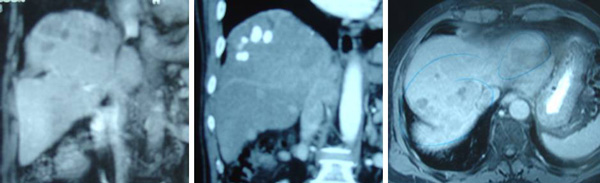

About three years later, KB felt a lump in his abdomen. CT scan on 23 June 2009 report is a follows:

“There is a previous segment 6/7 and 7/8 wedge liver resections. There are multiple foci of lipiodol uptake in the liver post chemoembolisation in keeping with multicentric hepatomas.  These range from 2 – 20 mm in size. There are several recurrent hypervascular foci noted scattered in the subdiaphragmatic region of the right lobe of liver ranging from 5-15 mm. Absent gallbladder (previous cholecystectomy). No evidence of abdominal lymphadenopathy.”

Another CT scan was done on 4 September 2009. The imaging report appeared exactly the same as the one written on 23 June 2009 with the following exception:

“There are several hypodense foci in the right subdiaphragmatic region ranging from 2-15 mm. Impression: several  hypodense lesions scattered in the subduaphragmatic region of the right lobe of liver, ? generating nodules, ? early hepatomas.

MRI was also done on 3 October 2009. The report appeared exactly the same as the CT scan reports of 23 June and 4 September 2010, with the following exception:

“There are multiple irregularly enhancing nodules scattered in both lobes of the liver with clustering in the right subdiaphragmatic regions ranging from 3- 20 mm. These are suspicious of multicentric hepatomas.”

The son told us: But he only told us this fact three years after the operation. The surgeon should have told us before he did the operation.  Disappointed KB decided to see another doctor in Ipoh. A total body CT scan was done on 10 August 2010. The report is a follows:

“There are multiple hypodense lesions seen within the liver affecting nearly the entire parenchyma, with clustering seen in the subdiaphagramatic region. This is suggestive of multicentric hepatoma. The area of involvement is worse than that seen in previous scans.